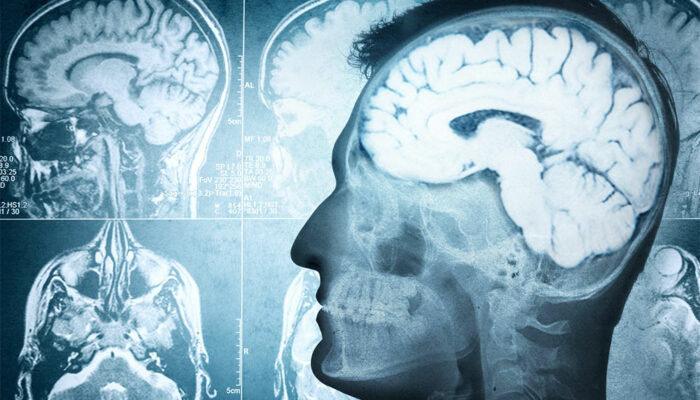

Effective ways to manage brain dysfunction

Aging is a natural, inevitable process. At best, it is possible to make continuous changes that complement and suit your current lifestyle. We are talking about changes in daily nutrition, habits, routine, and even finding dedicated health services and personal care assistance to improve quality of life. These changes are also beneficial in preventing and lowering the risk of certain progressive disorders that affect daily lifestyles. Here is an overview.

Studies show that 60% of the brain matter is made up of fat and nearly half of it consists of omega-3 fatty acids that boost and regulate cognitive function.

These healthy changes in nutrition boost cognitive development and slow down brain degeneration.